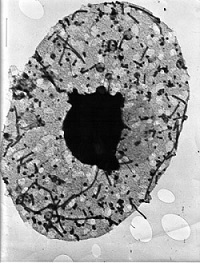

| Electron microscope image of the influenza virus--Courtesy of Olga Fišerová |

For the first time since the swine flu pandemic in 2009, influenza A virus pdm09 (pH1N1) predominated in the U.S. during the 2013-2014 flu season. And while this season saw overall lower levels of outpatient illness and death than in those predominated by fellow A virus H3N2, for older adults it was comparatively more severe, a CDC report found.